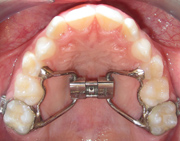

1). W-Expander (Quad or Bi- Helix): The purpose of the W-expander is to make the upper jaw wider. By expanding the upper jaw we can correct cross bites in the back of the mouth and create additional space to better align the adult teeth.